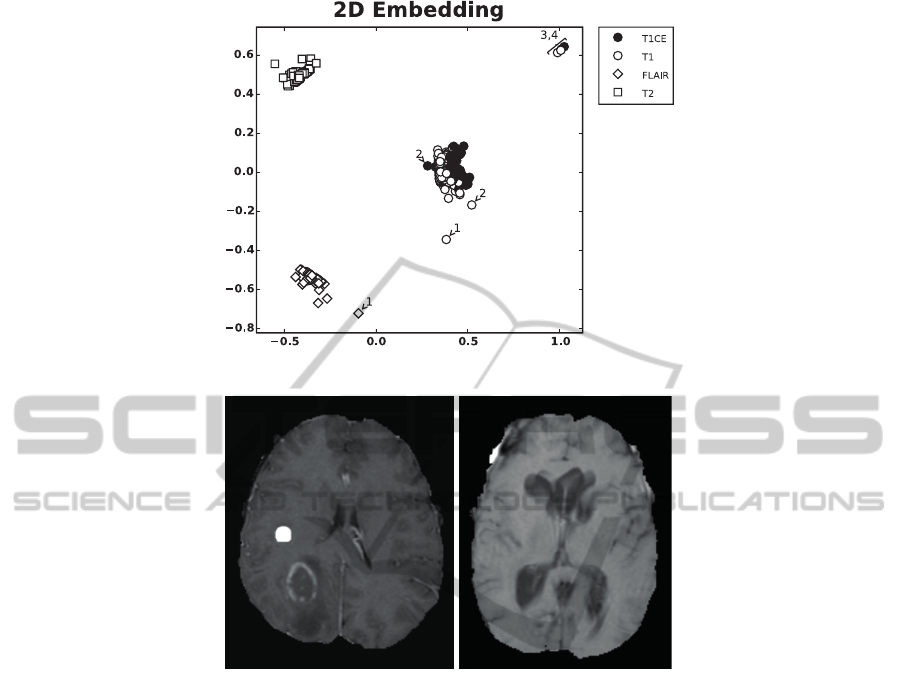

To demonstrate a potential application of the pro-

posed framework we compute the distance matri-

ces for N = 216 data sets from the BraTS 2014

training data (data set 2) and use the Isomap algo-

rithm (Tenenbaum et al., 2000) to perform a 2D em-

bedding (Fig. 3A). Based on the distance to the clus-

ter centers we were able to identify outliers. This is

shown for four cases (numbered 1 to 4 in Fig. 3A). To

confirm our hypothesis that the outliers correspond to

impaired data sets that do not meet quality standards,

we manually inspected them. Case 1 corresponds to

data set brats tcia pat313 1. This data set contains

no native T1 - instead the T2-FLAIR image was en-

closed twice. Case 2 (brats tcia pat216 1) misses

again a native T1 weighted image. Instead a contrast

enhanced image with spherical artifacts was included

(Fig. 3B left). Case 3 (brats tcia pat230 2) displays

severe motion artifacts in T1 (Fig. 3B right). Case 4

corresponds to brats tcia pat250 1 and does not con-

tain a native T1, instead a T1CE was included twice.

Note, even if only one channel is corrupted this

leads to changes of multiple entries in the distance

matrix and thus can affect the position of (all) other

channels in the low dimensional embedding.